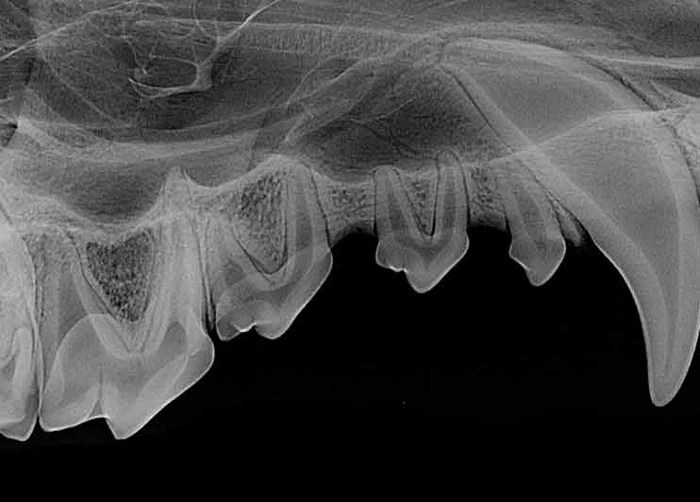

In both dogs and cats, the anatomical composition of the individual tooth is relatively the same. The tooth is made up of three portions: the lingual surface of the crown which is the visible portion above the gumline surrounded by enamel, the neck of the tooth (which includes the cementoenamel junction) or the region of the root between the crown and the attached gingiva, and the root which is the non-visible part embedded into alveolar (jaw) bone.

Enamel is the outer, strongest layer of the crown, which cannot regenerate once damaged. The dentin lies directly below the enamel and is what forms the bulk of the tooth, fully encapsulating the pulp cavity. The cementum is a thin covering of the root which provides anchorage for the periodontal ligament on the root. The pulp is the innermost, tissue contained within the tooth that is comprised of nerves, veins, arteries, and connective tissue. Finally, the apical delta is the apex portion of each tooth that allows for the passage of vessels and nerves in and out of the root canal.